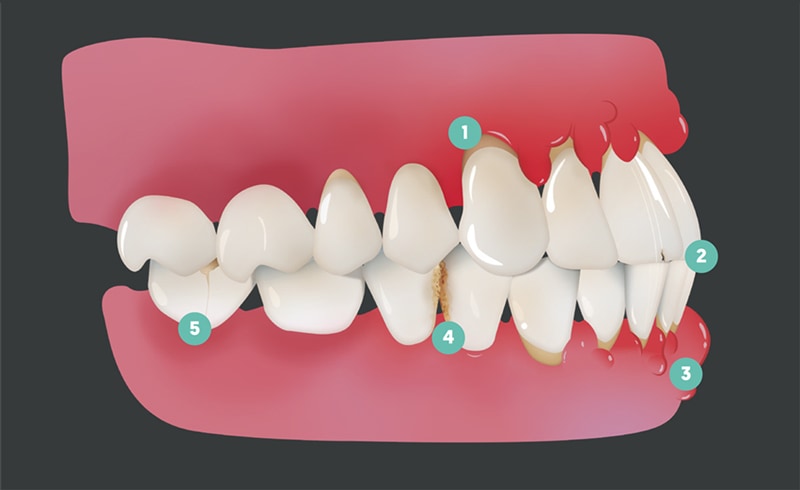

Tänderna är tänkta att passa ihop precis så som kugghjul i en maskin. När de inte linjerar rätt kan maskinen (du, i det här fallet) skada sig själv.

1. Abfractions tillskrivs oftast dem som gnisslar tänder, men om dina tänder är sneda kan detta ske utan att du är medveten om det.

2. Tandfrakturer kan bildas när dina tänder utsätts för upprepade påfrestningar.

3. Periodontal inflammation kan uppstå när tänderna sitter trångt och gör det svårt att hålla rent.

4. Tandförfall är enkelt att förstå. När dina tänder är trånga, fastnar maten lättare och förblir där längre, och dina tänder är helt enkelt svårare att rengöra. Det leder till karies, och ibland allvarligare former av tandrot.

5. Frakturerade fyllningar (och kronor och allt återställande arbete) kan vara resultatet av malocclusion. När dessa misslyckas kan de orsaka ytterligare skador på vad som finns kvar av tanden. Många av dessa problem kan hopas på varandra, och små problem kan snabbt förvärras.